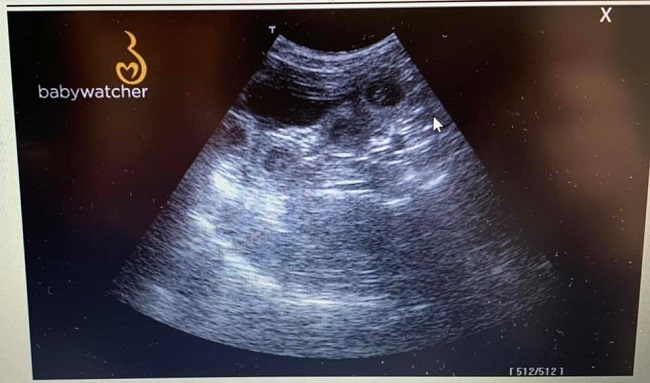

Hier noch einige Ultraschallbilder vom 22.02.2021 Es ist einiges los in Melodies Bauch und wir sind sehr gespannt was unsere Zaubermaus um den 27. März in die Wurfkiste legen wird. Jetzt heißt es erst mal unsere werdende Mama weiterhin ordentlich verwöhnen mit Streicheleinheiten, Bewegung und einigen Extraleckereien :-)

Dicht an dicht gekuschelt sitzen die J-chen gleichmäßig in den Gebärmutterhörnern verteilt.